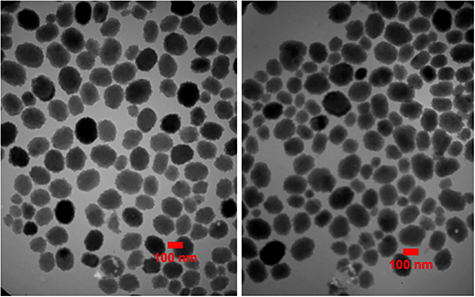

2.4.1. Transmission electron microscopy (TEM)

TEM was conducted to evaluate the morphology, size, and uniformity of niosomes according to the 3001-1503-7 standards at the specialized laboratory of the Sharif University of Technology, Tehran, Iran. One drop of niosome suspension was placed on a carbon-coated grid for 2 min and the excess liquid was removed using filter paper. One drop of 2% uranyl acetate aqueous solution was added to niosomes for negative staining. Samples were examined after 3 min at room temperature using a digital camera at 80 kV accelerating voltage. The pictures taken during TEM were analyzed by ImageJ bundled with Java 1.8.0_172 software (National Institutes of Health, http://imagej.nih.gov/ij). The mean diameter of niosomes was determined using the Cilas laser diffraction particle size analyzer (Model 1064, Cilas, France) at RT. The size modification of cefazolin-loaded niosomes stored in the original solution was measured and monitored at 4 °C every 3 months.

Standard image High-resolution image3.2. Niosomes characterization

TEM micrographs showed that the niosomes were spherical in shape with approximately uniform size. The size of niosomes measured by TEM was obtained around 100 nm, while the particle diameter of niosomes measured by DLS was about 137 nm. Size distribution (PDI) of niosomes showed a proper uniformity and monodisperse quality for the particles (figures 2 and 3). The surface charge of the niosomes containing drug was obtained around −63 mV (figure 4). No significant difference in morphology, size, zeta potential and PDI were found between cefazolin-loaded niosomes and its control (drug free niosomes). The niosomal formulation was stable during the storage conditions (at 4 °C, for 1 month) and there was no significant change in particle size, PDI, zeta potential and EE %.

Figure 2. TEM micrographs of cefazolin-loaded niosomes (left) and its control (right). The particle diameter of the niosomes was calculated by Image J software.